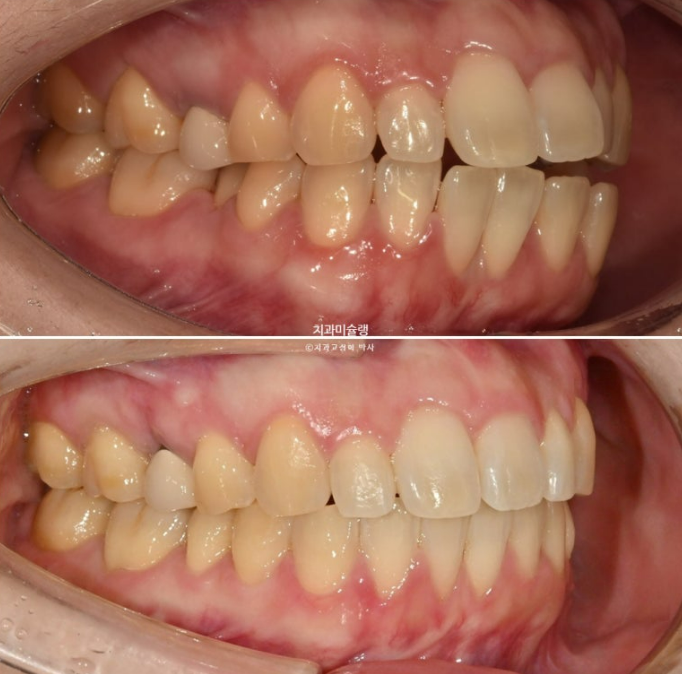

정중선 기준 한쪽만 개방교합이 있는데 한쪽방향으로 혀내밀기 습관때문에 생긴 개방교합일 수 있고 유지장치 변형에 의해 치열이 일그러진 것 일수도 있습니다.

소구치에 윗니와 아랫니가 엇갈려 물리는 가위교합도 보입니다.

파란화살표는 가위교합 원인 치아입니다.

어금니들이 사랑니 공간으로 순서대로 이동하며 공간이 생기는 중입니다.

안으로 쓰러졌던 작은어금니는 공간이 충분히 만들어 진 후 세우는 중입니다.

중심선이 아직 어긋나 있지만 개방교합은 해소가 되었습니다.

교합관계는 1급이지만 어금니 교합이 약간 떠있습니다.

배열은 좋습니다.

추가장치 이후 이제 중심선은 잘 맞습니다.

어금니 교합은 물샐틈 없는 1급 교합관계를 보입니다.

24.06~25.11